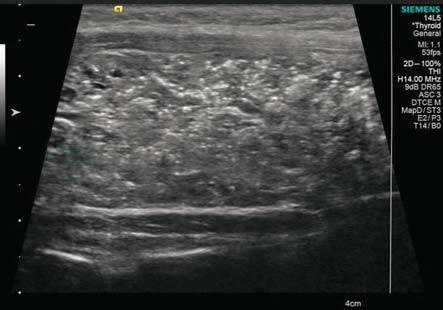

图3-1 甲状腺测量

最大横切面测量前后径和左右径

(1)甲状腺测量一般是在灰阶超声条件下进行。每侧甲状腺应在横切面测量左右径和前后径两个径线,峡部应测量前后径,必要时可在纵切时测量甲状腺上下径,如测量有困难可使用宽景成像或梯形成像功能进行。

(2)在做侧叶从上至下滑行横切时,观察其最大横切面,测量侧叶前后径和左右径(图3-1);颈前正中横切,确定峡部最大厚度的切面后,冻结图像,测得峡部厚度(图3-2);侧叶纵切时,也采用滑行的方法确定最大纵切面,测量上下径(图3-3)。

(3)甲状腺测值过程中需要强调三点:①扫查时探头保持与皮肤垂直,否则会高估甲状腺的前后径;②同时探头一定要轻放于皮肤上,否则会导致左右径的高估,而前后径的低估;③横切时,探头应尽可能处于水平状态,否则会高估甲状腺的左右径。